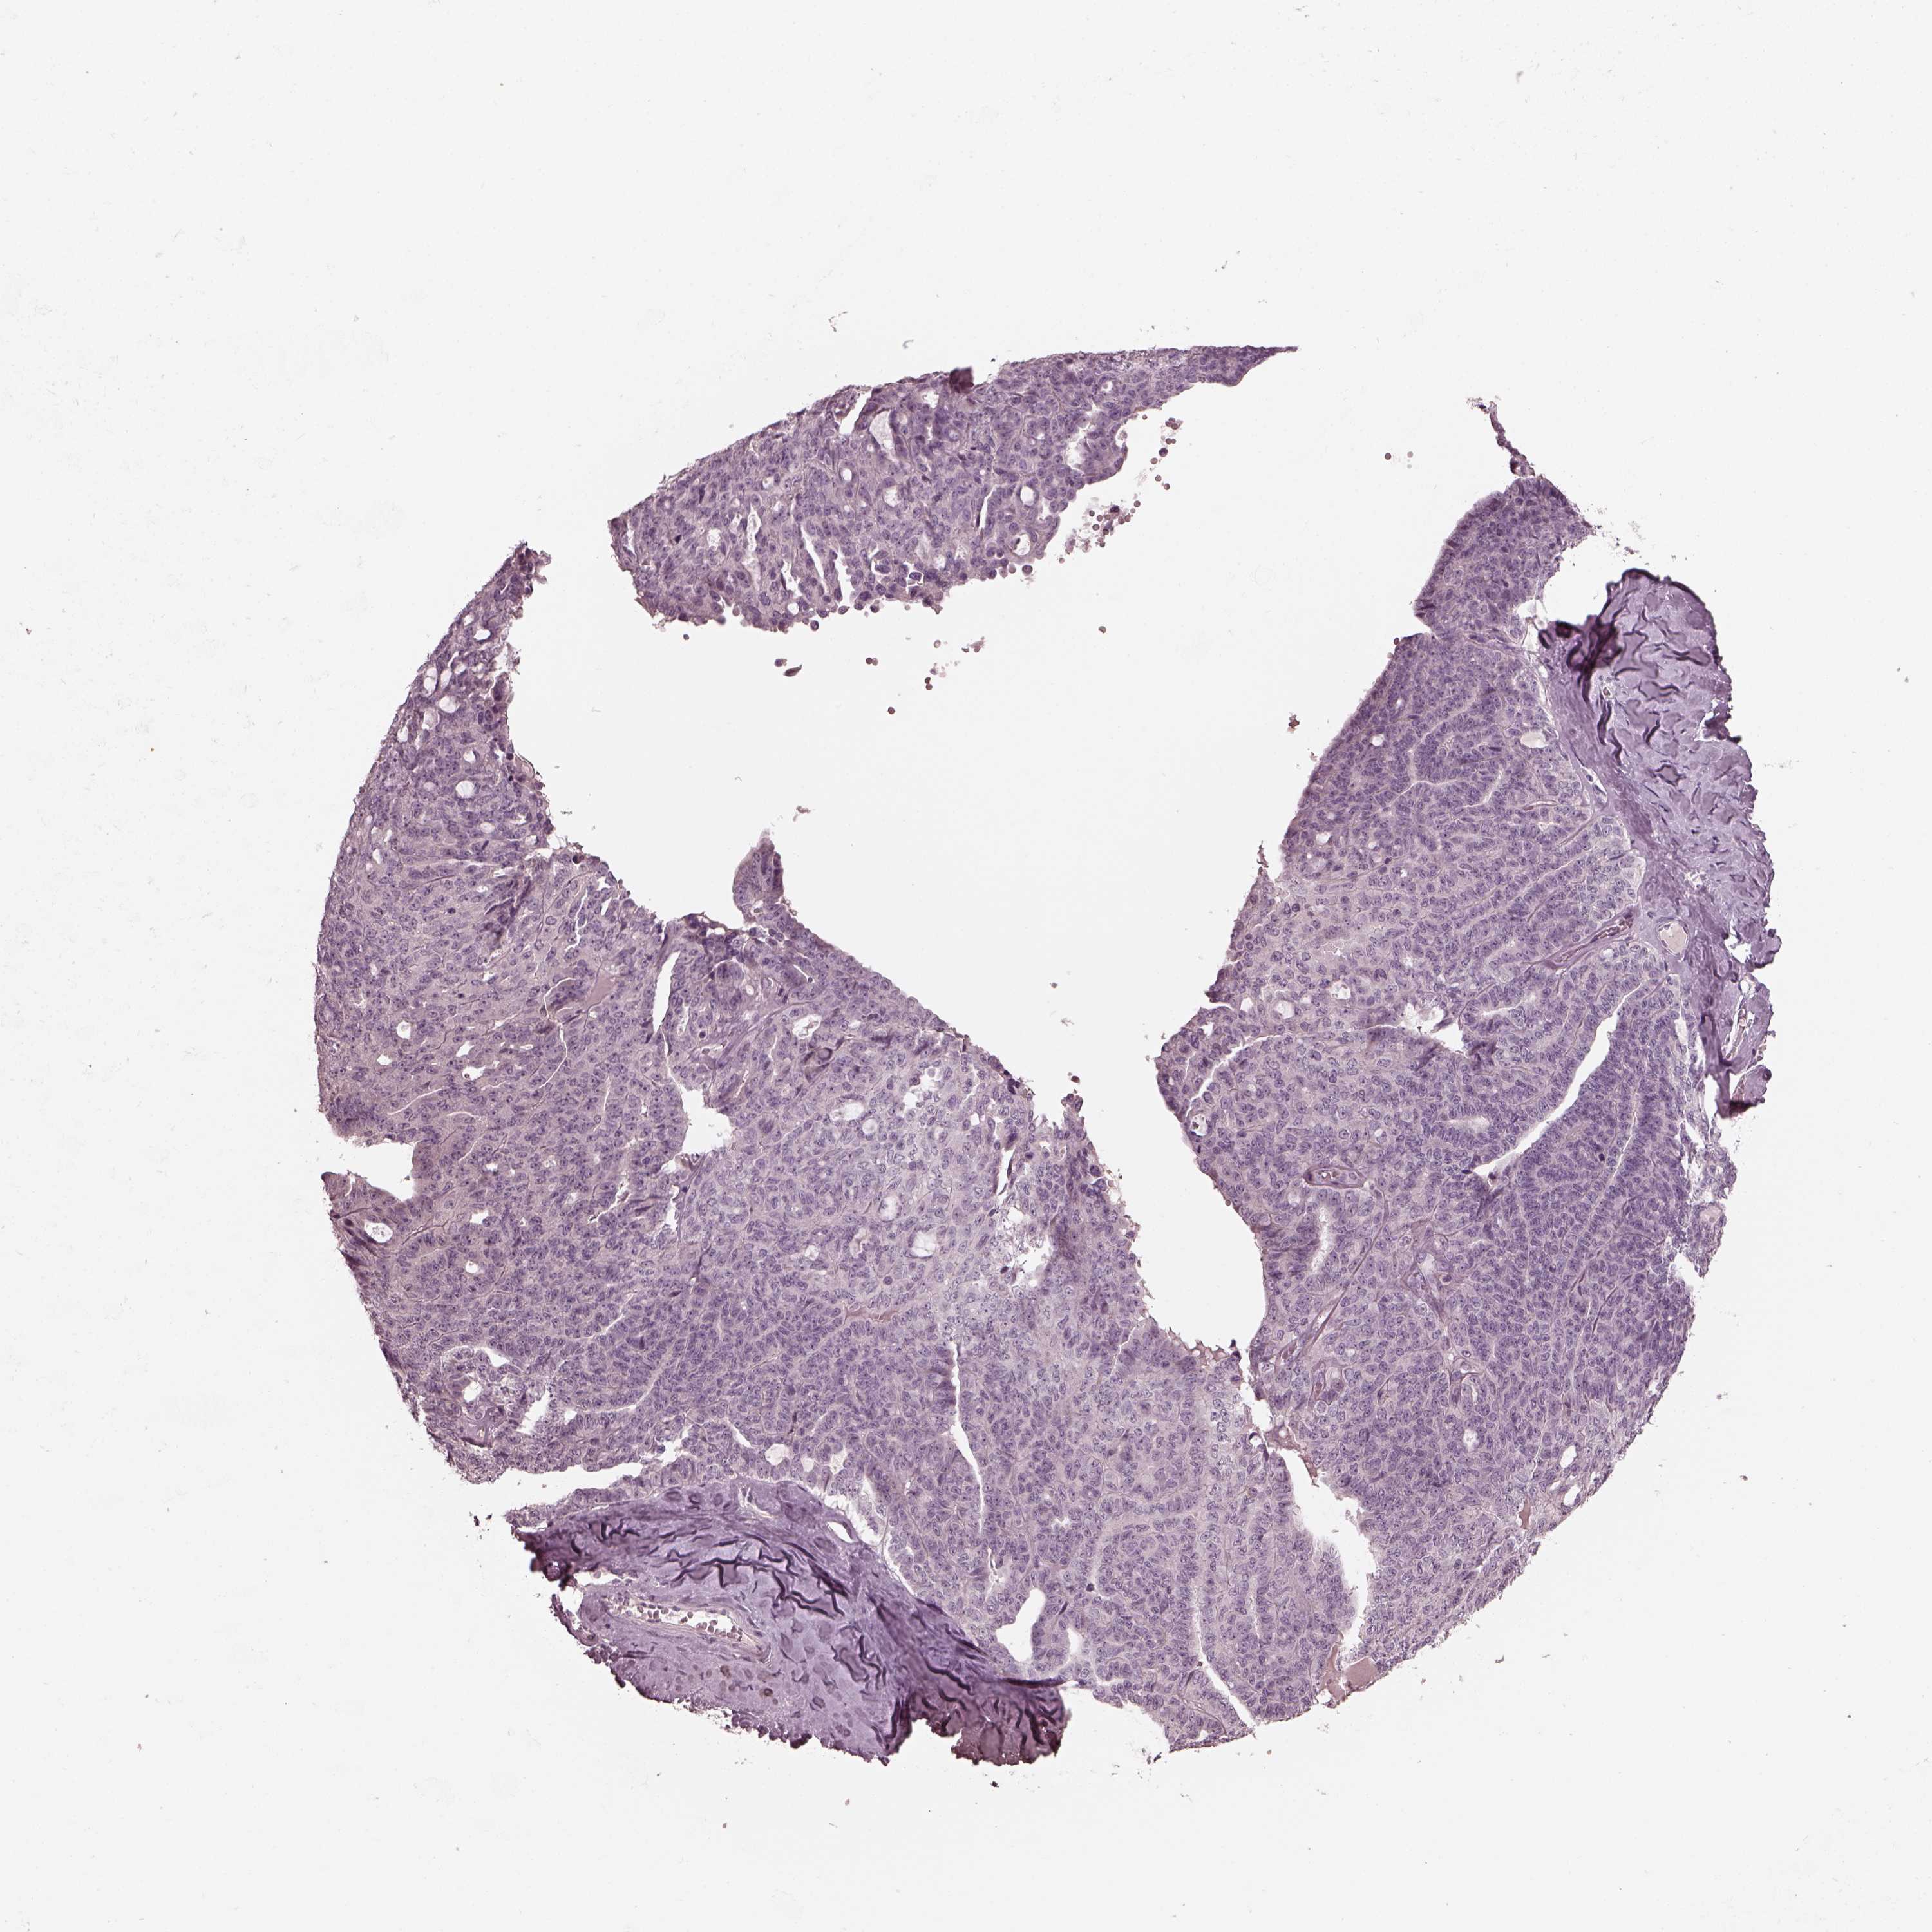

OVARIAN CANCER - Protein expressioni

A mouse-over function shows sample information and annotation data. Click on an image to view it in a full screen mode. Samples can be filtered based on level of antibody staining by selecting one or several of the following categories: high, medium, low and not detected. The assay and annotation is described here.

Note that samples used for immunohistochemistry by the Human Protein Atlas do not correspond to samples in the TCGA dataset.

Antibody stainingi

Antibody staining in the annotated cell types in the current human tissue is reported as not detected, low, medium, or high, based on conventional immunohistochemistry profiling in selected tissues. This score is based on the combination of the staining intensity and fraction of stained cells.

Each image is clickable and will lead to virtual microscopy that enables deeper exploration of all samples and also displays staining intensity scores, fraction scores and subcellular localization as well as patient and tissue information for each sample.

Antibody HPA015783

Antibody CAB022363

Cystadenocarcinoma, serous, NOS

Cystadenocarcinoma, mucinous, NOS

Carcinoma, endometroid